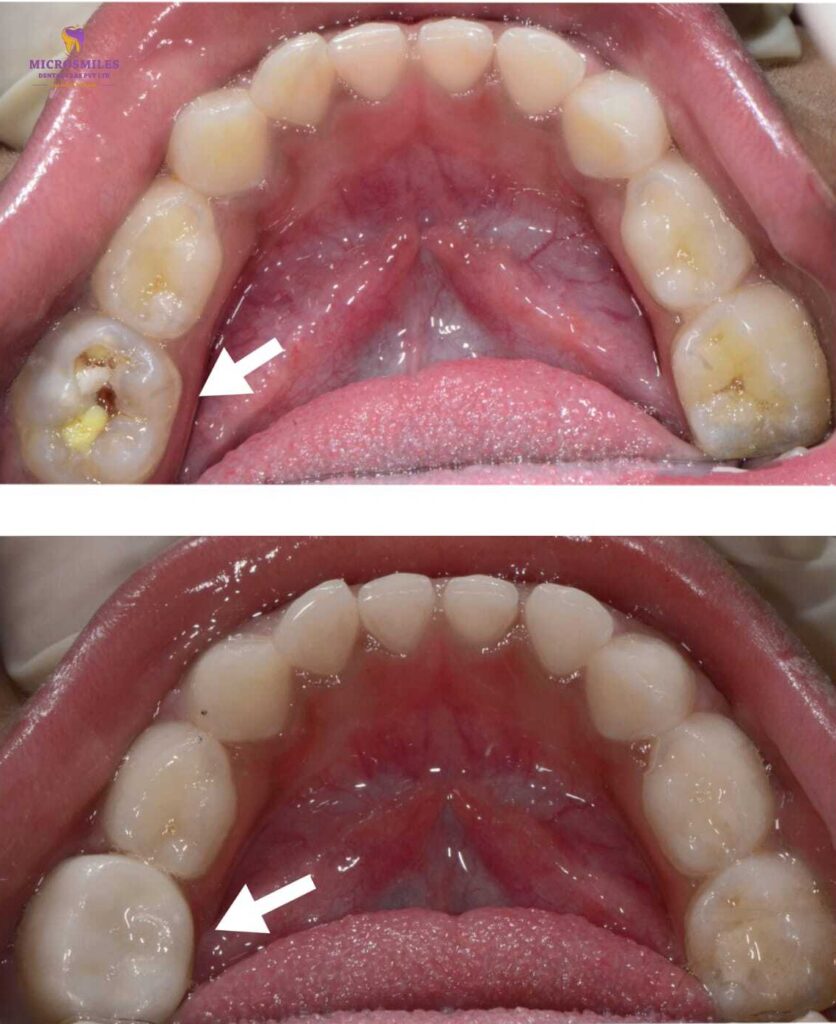

When your child’s tooth needs more than a filling, you want a solution that’s strong, safe, and looks just like a natural tooth. At Microsmiles Dental Care, our Zirconia Crowns / Ceramic Caps are the ideal choice for restoring damaged or decayed baby teeth-without compromising on appearance or comfort.

These aesthetic, child-friendly crowns offer long-term protection with a natural look that keeps your child’s smile bright and confident.

While stainless steel crowns are functional, they often leave a metallic look. Zirconia crowns, on the other hand, offer the strength of metal with the beauty of ceramic, making them the preferred choice for visible front teeth or parents seeking a more natural aesthetic.